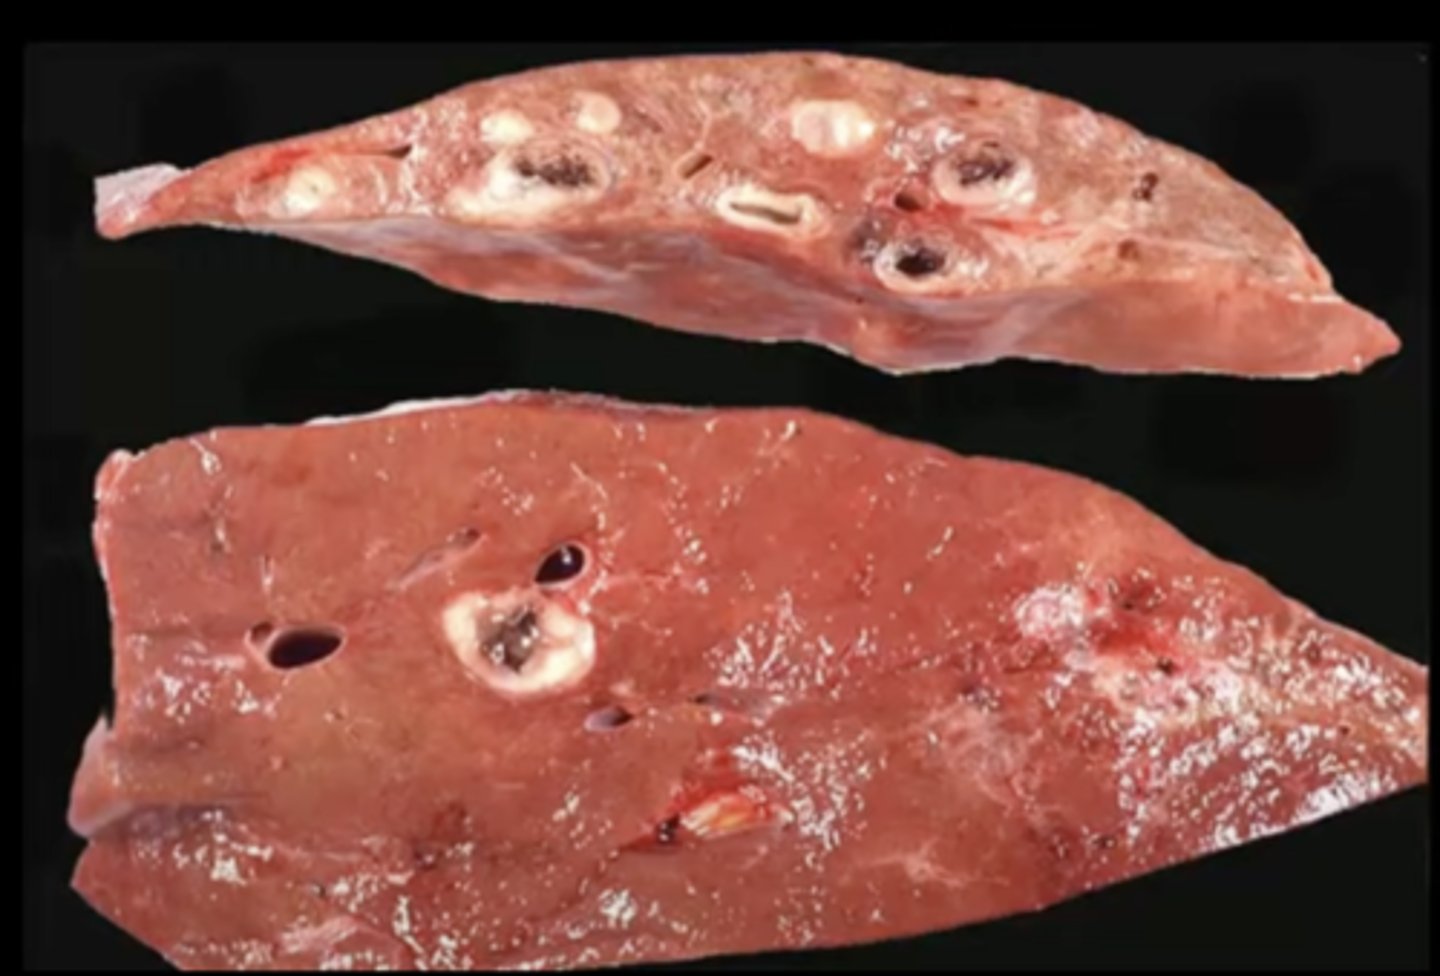

Flukes!!

-migration of flukes through liver parenchyma

What caused this lesion in the liver of a deer?